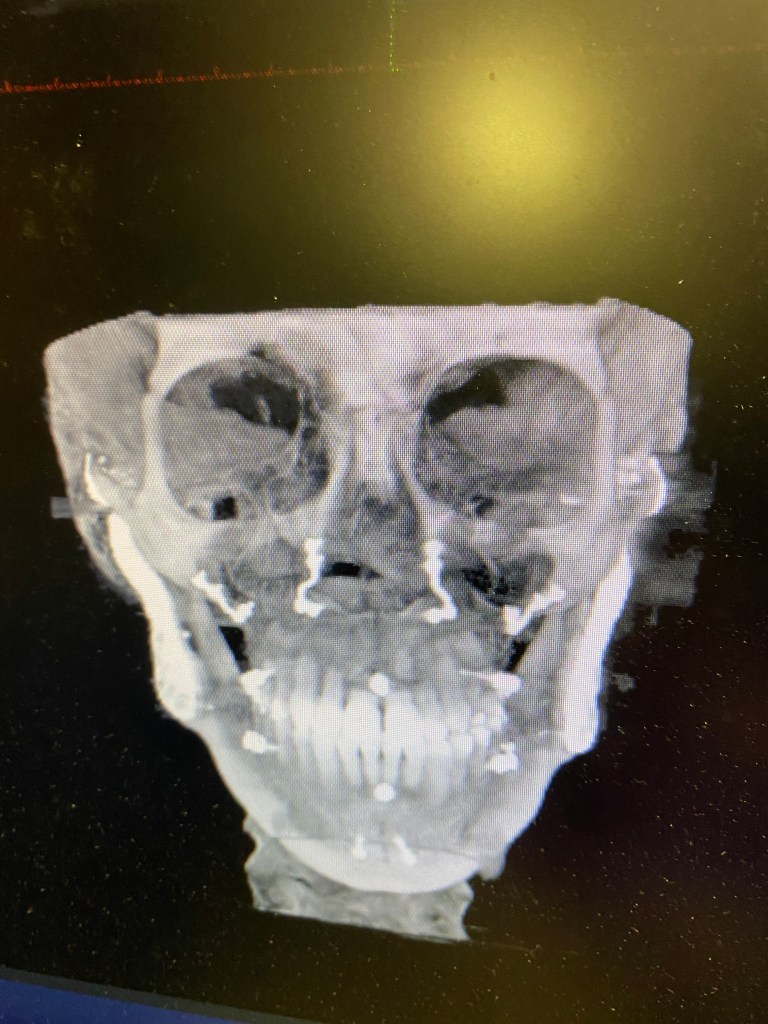

It has been a FULL WEEK since my surgery!! It feels like it has gone by so fast! First off, I want to start this post by showing my first before and after Xray which I couldn’t be happier about!! Look at that airway. I am so thankful now that this surgery was an option for me. I spent a long time rightfully being scared of it, but did the amount of research I felt comfortable with and felt like I knew my own personal pain / TMJ issues well enough going into it to to decide for myself if I thought it would give me a better shot at living. It took me a full year to fully research, consult with 4-5 different jaw surgeons, and talk with anywhere from 100-200 patients online (I’m not even kidding. I am very careful with my health and decisions after what happened to me in the past with jaw treatments and extreme orthodontic work). I was talking with one of my good ICR friends a while back who also researches a lot and we kind of laughed that we envy the people who go into this blind and just get perfect results. No worry or anxiety.

- Airway: Before I had TJR, my airway was 2mm at the narrowest point as

- Forward Head Posture/ cervical spine: As the mandible dips back from ICR, it presses on the airway causing the head to tilt forward and the neck to crane in order to open up the soft tissue of the airway enough to receive adequate oxygen. I’m so thankful the body adapts, but these adaptations are not without consequences and many of the consequences we still don’t medically have a good grasp on to know just how far reaching they are to other systems in the body.

- My post op x-ray shows a straighter head posture! I have been seeing a chiropractor the past few years to help manage some of my chronic pain, so I imagine he will be very happy to see this!

- Lips are closed: It is HEALTHY to breathe through the nose and to have your lips closed. Those with ICR are unable to do this without muscle strain, which encourages mouth breathing. Mouth breathing causes all. kinds. of. problems. You can read more about them here if you are interested: https://www.endur.com/blogs/blog/8-scary-consequences-of-mouth-breathing